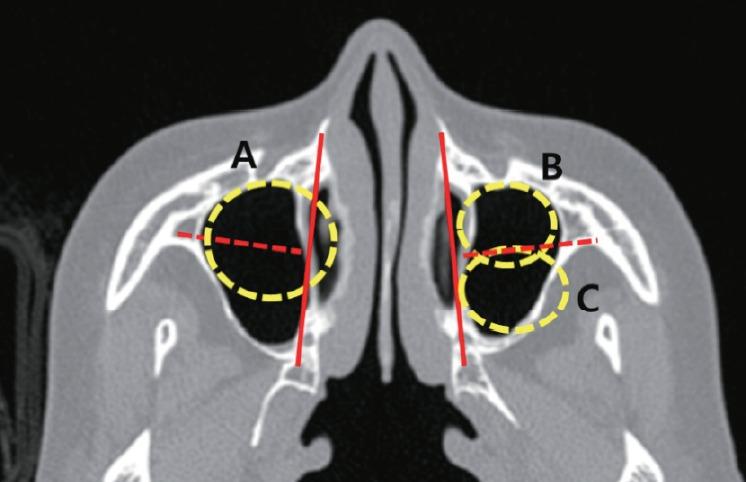

Postoperative cheek cyst (POCC) is a late postoperative complication of radical maxillary sinus surgery including the Caldwell-Luc (C-L) operation. The present study aimed to evaluate the therapeutic outcomes of surgical treatment for POCC and to assess the clinical factors correlated to these outcomes.

This study included 57 patients (67 nostrils) diagnosed with POCC who underwent surgical drainage. The medical records of the patients were retrospectively reviewed for radiological findings, treatment modalities, residual symptoms, and recurrences.

In total, 30 patients were male and 27 patients were female with a mean age of 55 years, and the patients were usually diagnosed with POCC 28.2 years after radical surgery. Endonasal endoscopic marsupialization was performed via inferior meatal antrostomy, and if possible, middle meatal antrostomy was performed at the same time. In patients with cysts that were difficult to reach using an endonasal endoscopic approach, additional open C-L approaches were performed. The median follow-up period was 19.4 months. Overall, adequate drainage and symptomatic relief were achieved in 91% (61/67) of the patients. The recurrence rate was significantly higher in patients who had anterolateral POCC. Failure to achieve symptomatic relief was correlated to a smaller cyst and the use of the open C-L approach for drainage.

The location and size of the cyst as well as the use of the open surgical approach were important factors in predicting the therapeutic outcome of POCC. The time point of treatment and surgical approaches should be based on the above-mentioned findings.